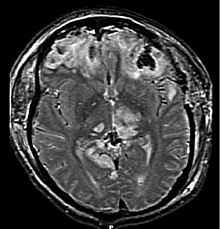

Hematomas, also focal lesions, are collections of blood in or around the brain that can result from hemorrhage.[24] Intracerebral hemorrhage, with bleeding in the brain tissue itself, is an intra-axial lesion. Extra-axial lesions include epidural hematoma, subdural hematoma, subarachnoid hemorrhage, and intraventricular hemorrhage.[105] Epidural hematoma involves bleeding into the area between the skull and the dura mater, the outermost of the three membranes surrounding the brain.[24] In subdural hematoma, bleeding occurs between the dura and the arachnoid mater.[32] Subarachnoid hemorrhage involves bleeding into the space between the arachnoid membrane and the pia mater.[32] Intraventricular hemorrhage occurs when there is bleeding in the ventricles.[105]